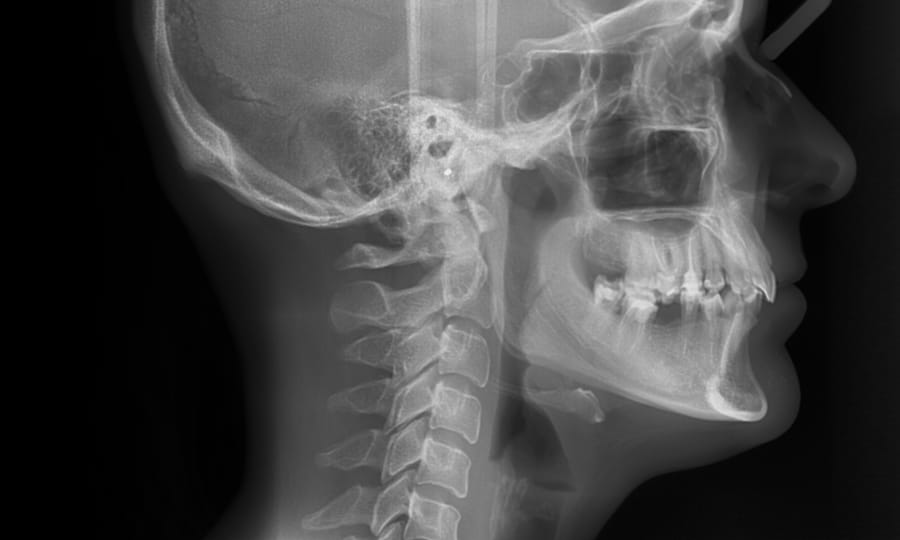

Cephalometric X-rays

A cephalometric X-ray is a specialized image that shows a side view of your head, including your teeth, jaw, and facial profile. This type of imaging helps your orthodontist understand how your teeth and jaw relate to each other and to your facial structure.

Cephalometric X-rays are frequently used to assess jaw growth, identify misalignments, and plan orthodontic treatments such as braces or aligners. They also help monitor changes over time, ensuring your treatment advances as planned and your bite stays in harmony with your facial proportions.